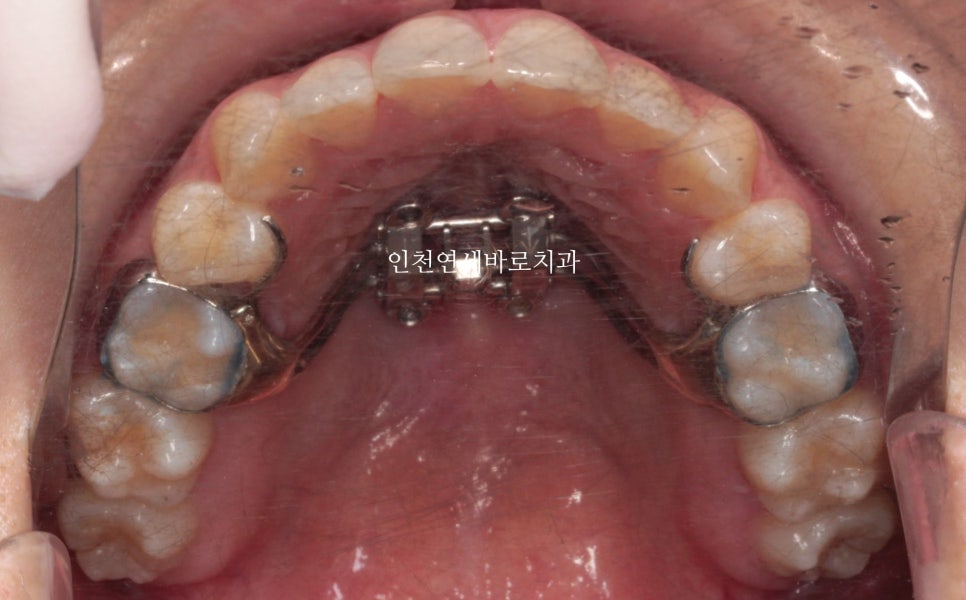

악궁확장장치 #mse 도 사용하였습니다.

이후 #인비절라인 으로 치료를 시작했습니다. 그때가 2020.6.30.